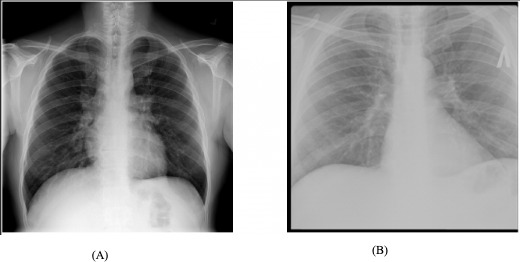

Objective: This study aimed to evaluate the performance of 6 convolutional neural network architectures-Visual Geometry Group-16 (VGG16), VGG19, Residual Network-50 (ResNet50), ResNet101, ResNet152, and Inception-ResNet-V2-in classifying chest x-ray (CXR) images as either normal or TB-positive. The impact of data augmentation on model performance, training times, and parameter counts was also assessed.

Methods: The dataset of 4200 CXR images, comprising 700 labeled as TB-positive and 3500 as normal cases, was used to train and test the models. Evaluation metrics included accuracy, precision, recall, F1-score, and area under the receiver operating characteristic curve. The computational efficiency of each model was analyzed by comparing training times and parameter counts.